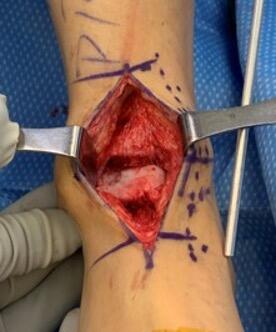

The incision was the typical anterior ankle approach. This would limit location of incisions for potential future issues or conversion to fusion or total implant. We then exposed the distal tibia and dorsal neck of the talus. Placing the prefabricated custom cut guide onto the neck of the talus, we then checked this under fluoroscopy to ensure placement, and the proper orientation and amount of lateral dome to be removed. We then pinned this guide in place with predetermined holes. A reciprocating blade limited blade excursion and minimized potential for injury to adjacent structures. After removal of the damaged piece of talus we placed the trials. The goal was to have the trial flush or even slightly recessed with regard to the adjacent cartilage. During weight bearing, the native cartilage will compress, so it is important to match the weight bearing level. If the implant is proud, then during weight bearing the cartilage will naturally compress, but the implant will not, potentially giving rise to issues with load bearing around the device.